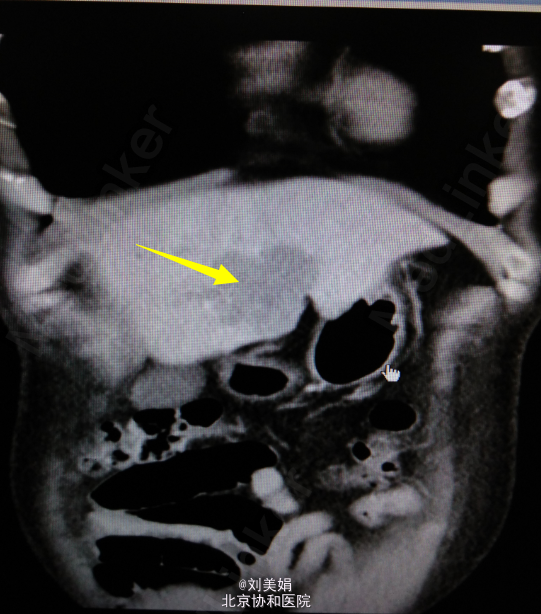

患者 男 58岁 主 诉:乙肝20余年,发现肝脏占位1月余 现病史:患者乙肝病史20余年,间断口服保肝药物,并定期复查肝功,肝功能目前可。每年常规行腹部B超检查,均未见明显异常。1月前体检,行腹部CT发现肝脏占位。患者无畏寒发热、腹痛腹胀、恶心呕吐、皮肤黄染等。于2015年7月10日我院门诊就诊,行腹部增强CT+三维重建示:肝左叶见不规则状稍低密度影,最大截面约为6.0cm×4.6cm,增强后动脉期可见明显强化,门脉期及延迟期强化程度减低,呈“快进快出”强化,肝左动脉分支参与病变供血,门静脉左支局部明显变细,肝门区、小网膜囊内、腹膜后多发淋巴结,部分增大。考虑:肝左内叶占位,考虑恶性病变可能性大;肝左动脉分支参与病变供血,门静脉左支局部明显变细,局部受累可能;肝门区、小网膜囊内、腹膜后多发淋巴结,部分增大。肝肾功:AST 67U/L,LD 254U/L,TBil 13.2μmol/L,DBil 4.5μmol/L,Cr(E) 79μmol/L,ALT 45U/L,Alb 48g/L,GGT 47U/L。

腹部增强CT+三维重建:肝左内叶占位,考虑恶性病变可能性大;肝左动脉分支参与病变供血,门静脉左支局部明显变细,局部受累可能;肝门区、小网膜囊内、腹膜后多发淋巴结,部分增大;双肾多发结石;左肾小囊肿;腹主动脉及其分支动脉粥样硬化性改变;胸腰椎骨质增生。